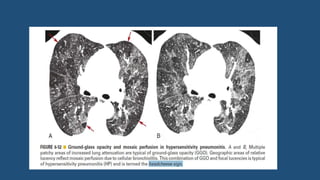

Hypersensitivity pneumonitis

• HRCT finding in sub-acute HP

• Patchy or geographic GGO (80%)

• Poorly defined centrilobular GGO nodules

• Upper or mid-lung predominance, with involvement of the entire cross-

section of the lung (i.e., there is no subpleural predominance)

• Mosaic perfusion caused by bronchiolar obstruction

• Air trapping (commonly present on expiratory Scans)

• A combination of patchy GGO and patchy mosaic perfusion (termed the

headcheese sign) : typical of HP